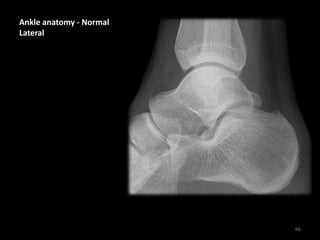

Ankle anatomy - Normal

Lateral

66

• Carefully following the

bone contour of the

tibia and fibula shows

the inferior edge of the

medial and lateral

malleoli